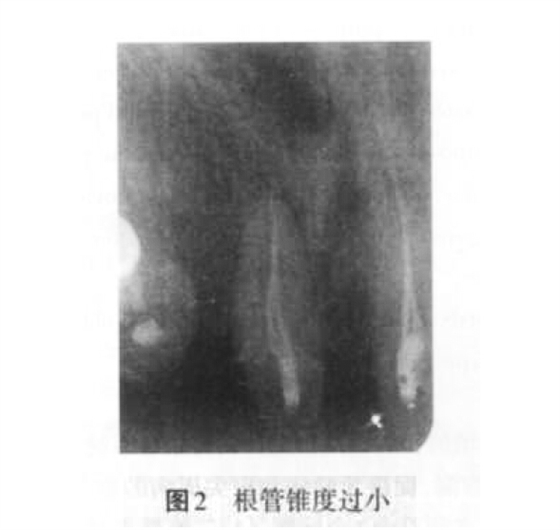

2. 1 充填不致密的原因 主要是因?yàn)楦茴A(yù)備不足、根管錐度過(guò)小(圖2)、未根據(jù)患牙根管形態(tài)的特點(diǎn)合理選擇根充材料和技術(shù)。此外,術(shù)者操作不當(dāng)也是導(dǎo)致根充不致密的原因之一。